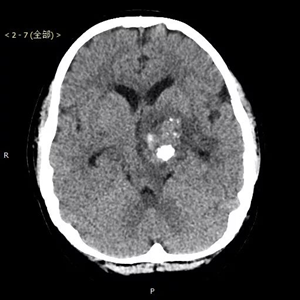

患者,男,入院时间2016年8月9日,入院时年龄13岁5月24天。主诉:右腿晃动3个月,伴右侧肢体力量减弱2个月。术后病理显示为囊性成熟型畸胎瘤,肿瘤组织内神经胶质细胞成分、平滑肌及腺上皮成分细胞异质性明显。

患者来到北京儿童医院就医时,由于肿瘤压迫脑功能区导致了瘫痪。北京儿童医院神经外科葛明教授及团队,对其进行了全切除手术,肿瘤直径4公分左右,手术路径深十公分左右,分块切除,历时四小时完整切除。术后患者瘫痪状态消失,随访恢复良好。

患者术后资料(下图)